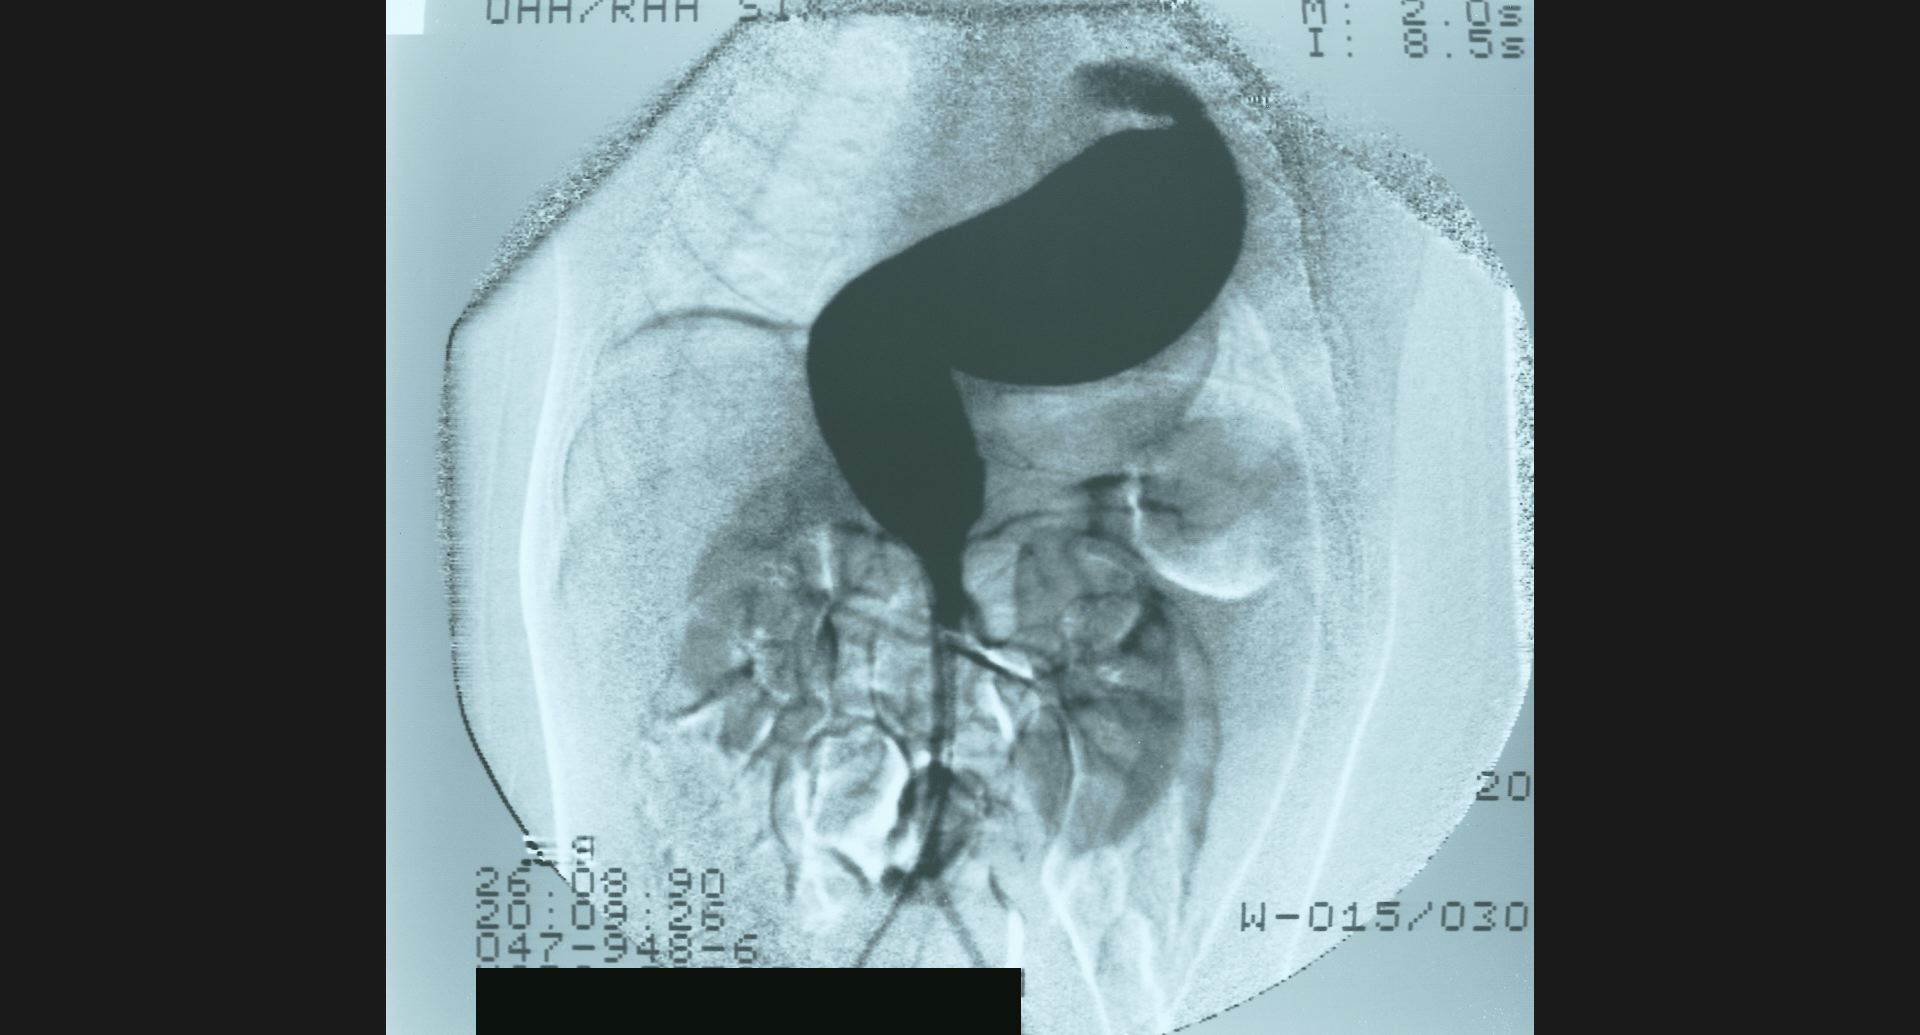

fig.12(73KB) :LC (arterial portography)